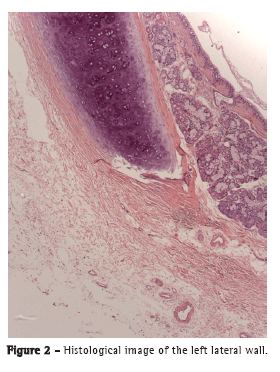

The OCT images were able to delineate, in real time, microstructures, such as the epithelium, submucosa, and cartilage, as well as the adventitia (Figure 1) of the anterior and lateral tracheal walls, similarly to the images produced by conventional histology (Figure 2). In the posterior wall, the layers corresponding to the mucosa, submucosa, and trachealis muscle were clearly differentiated on the OCT images (Figure 3) and were consistent with the histological images (Figure 4).

Imaging with OCT allowed real-time identification of microstructures, such as the epithelium, submucosa, and cartilage, as well as the adventitia of the anterior and lateral tracheal walls. In the posterior wall, it was possible to identify the mucosa, submucosa, and trachealis muscle.